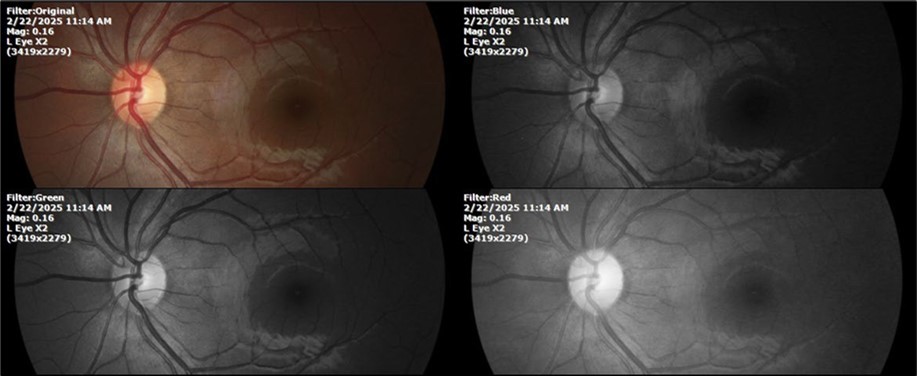

There is no pain, only minimal discomfort, and my vision has improved (Figure 20, Figure 21, Figure 22, Figure 23, Figure 24)

Figure 20.The mirror reflection of the affected (right) eye continues to improve.

Figure 21.The anterior segment of the right eye responds with difficulty to mydriatics, which is usual in diseased eyes.

Figure 22.The whitish mass of phantom cells continues to decrease. The treatment continues to be based on ǪIAPI 1®, sublingual drops, three drops every hour, for as long as the patient is awake.

Figure 23.The mirror reflection of the left eye, without anomalies.

Figure 24.The eye that was not affected by the trauma (left side) remains in good condition.